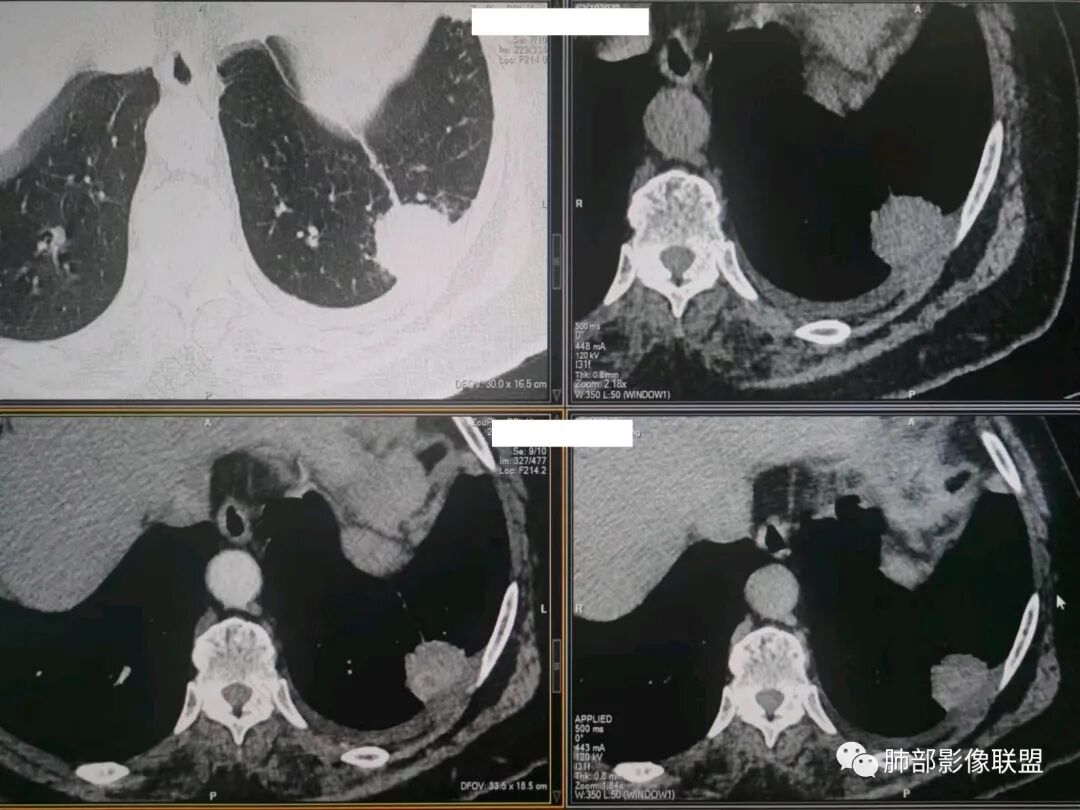

这就栽赃。都突到外面去了。

看看这个,骨头都侵袭了。

我只是邓较瘦:南大这个我感觉局部似乎是栽赃呢 箭头那里是啥?

南边:栽赃是这样过去的,中间不会脂肪间隙清晰。

胸壁的组织,除非你怀疑胸壁转移结节。

转移淋巴结。

局部侵犯。有差异。

我只是邓较瘦:这个是侵犯出去不是淋巴结吧?

南边:不是,你看看强化与淋巴结不一致。

我只是邓较瘦:强化与肿瘤差不多。

南边:是。